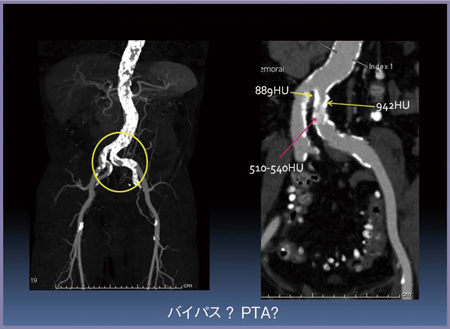

■PTA術前評価

症例5は,左ABI低下が指摘された症例で,左CIA(総腸骨動脈)に強度の石灰化を伴う90%狭窄が認められる。硬い石灰化の中にCT値500HU程度の非常に軟らかい石灰化があることが確認されたため,本症例はバイパス術ではなくPTAを選択した(図11,12)。

石灰化プラークであっても,CT値が低ければバルーンで拡張することができる。PTAとバイパス術では患者さんの負担が大きく異なることから,プラークの性状評価はきわめて重要である。

図11 症例5:PTA術前の石灰化の評価

(左CIA石灰化病変)